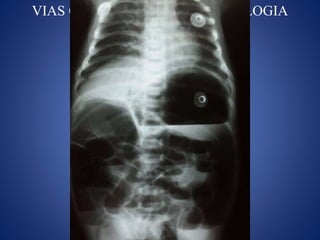

COMPLICACIONES

VIAS CENTRALES ENNEONATOLOGIA COMPLICACIONES